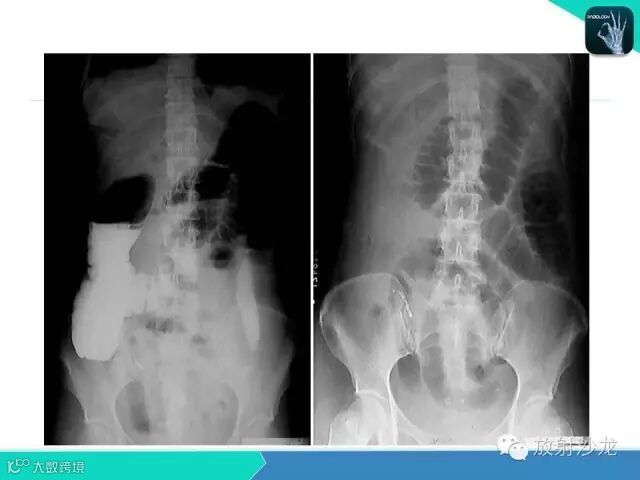

肠梗阻的分类及影像诊断